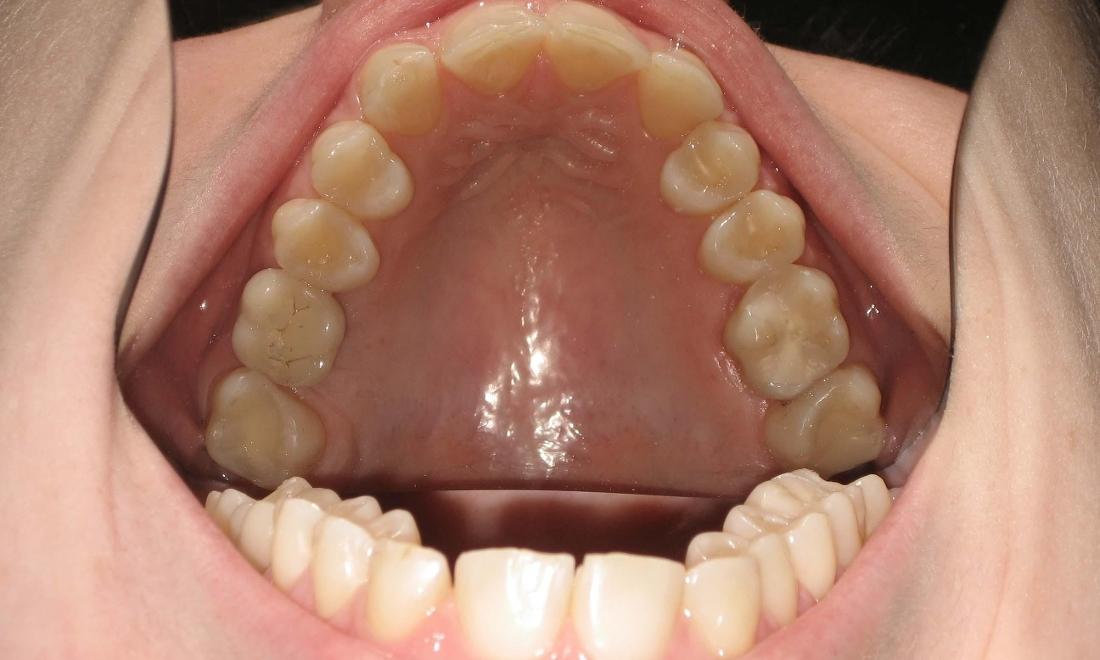

After